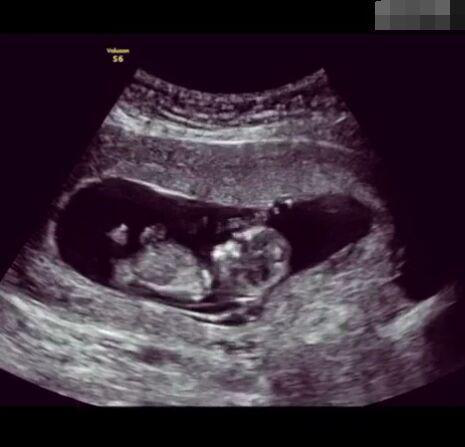

懷孕后,寶寶的性別一直是全家人的重點(diǎn)關(guān)注對(duì)象。而男女性別的差異,在基因?qū)用骟w現(xiàn)在第二十三對(duì)染色體上,如果是XY則是男孩,XX則是女孩,這都是由那枚與卵子結(jié)合的精子來決定。

圖片8.png

那些做了B超檢查確定胎兒男女,生下來后發(fā)現(xiàn)不對(duì)的,多半是因?yàn)樵贐超檢查時(shí)寶寶太調(diào)皮,以致影響了檢查準(zhǔn)確性。就比如說,有的女寶寶在媽媽肚子里玩自己的臍帶,把臍帶夾到了兩腿中間,B超就有一定幾率拍出來好像是男寶寶的特征,導(dǎo)致被誤認(rèn)為是男孩子。還有些男寶寶過分害羞,在做B超時(shí)雙腿緊緊并攏,醫(yī)生也很難判斷男女,只好大致猜測(cè)是女孩,就又造成了誤會(huì)。因此,B超亦不是萬能的。